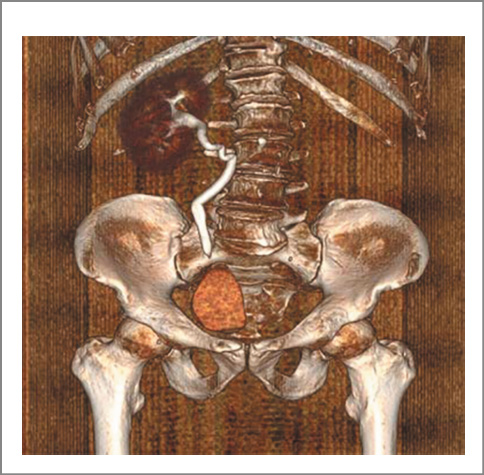

Наряду с ДМП выявлена аномалия в виде аплазии левой почки. В правой почке определена простая субкапсулярная киста объемом 15 см3. Объем предстательной железы составил 18,2 см3. При урофлоуметрии максимальная скорость мочеиспускания равнялась 15,0 мл/с, средняя – 8 мл/с при объеме мочеиспускания 210 мл. В перечень выполненных исследований вошли КТ живота и таза с контрастированием, микционная цистография и фиброуретроцистодивертикулоскопия. При последнем исследовании устье левого мочеточника не выявлено (рис. 3–6).

Рис. 3. Пациент В., компьютерная томограмма живота и таза: a – аплазия левой почки, ДМП; b – ДМП.

Рис. 4. Пациент В., 3D-реконструкция аплазии левой почки и левого мочеточника.